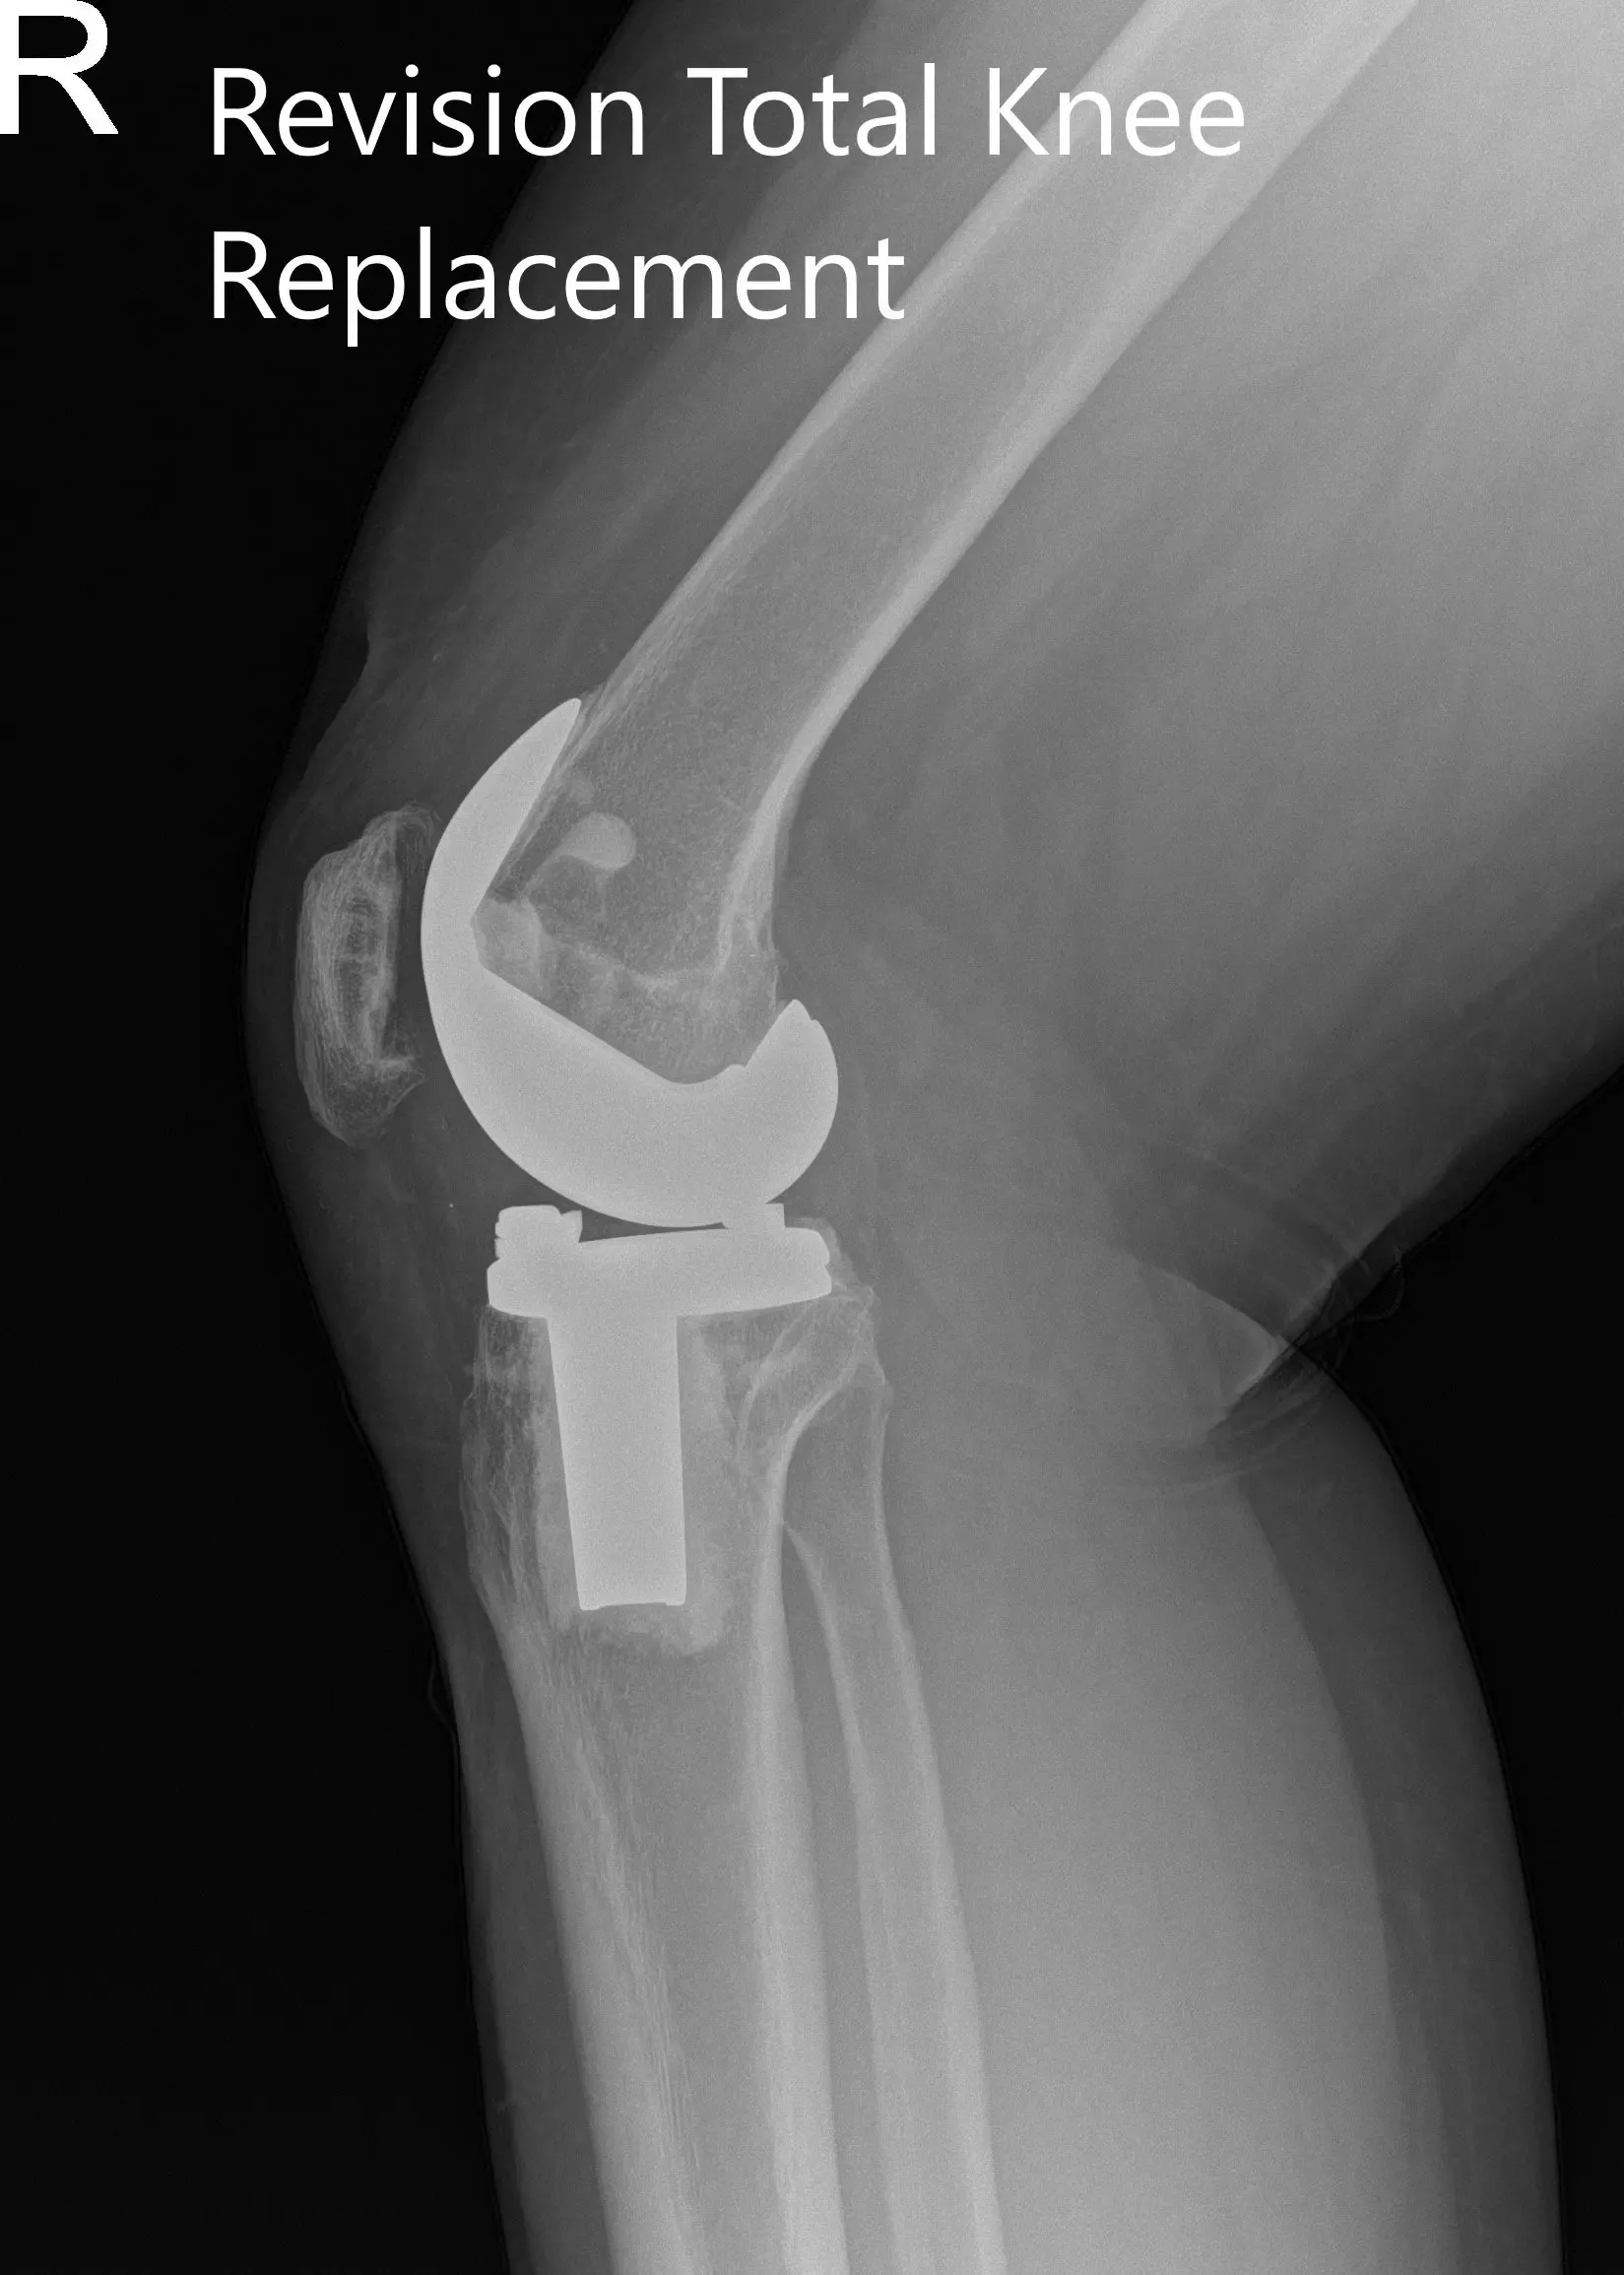

Postoperative x-ray showing the anteroposterior and lateral views of the right knee.

Post op his recovery was excellent. The pain was managed well with medications and he was ambulatory the same day of the surgery. He was given aspirin for deep vein thrombosis prophylaxis. He was advised physical therapy and home exercise program.

The sutures were removed uneventfully. The patient demonstrated a full range of motion with no pain at three months. The patient was able to walk without support and do her daily activities with ease. She was extremely happy with the outcome of the procedure.